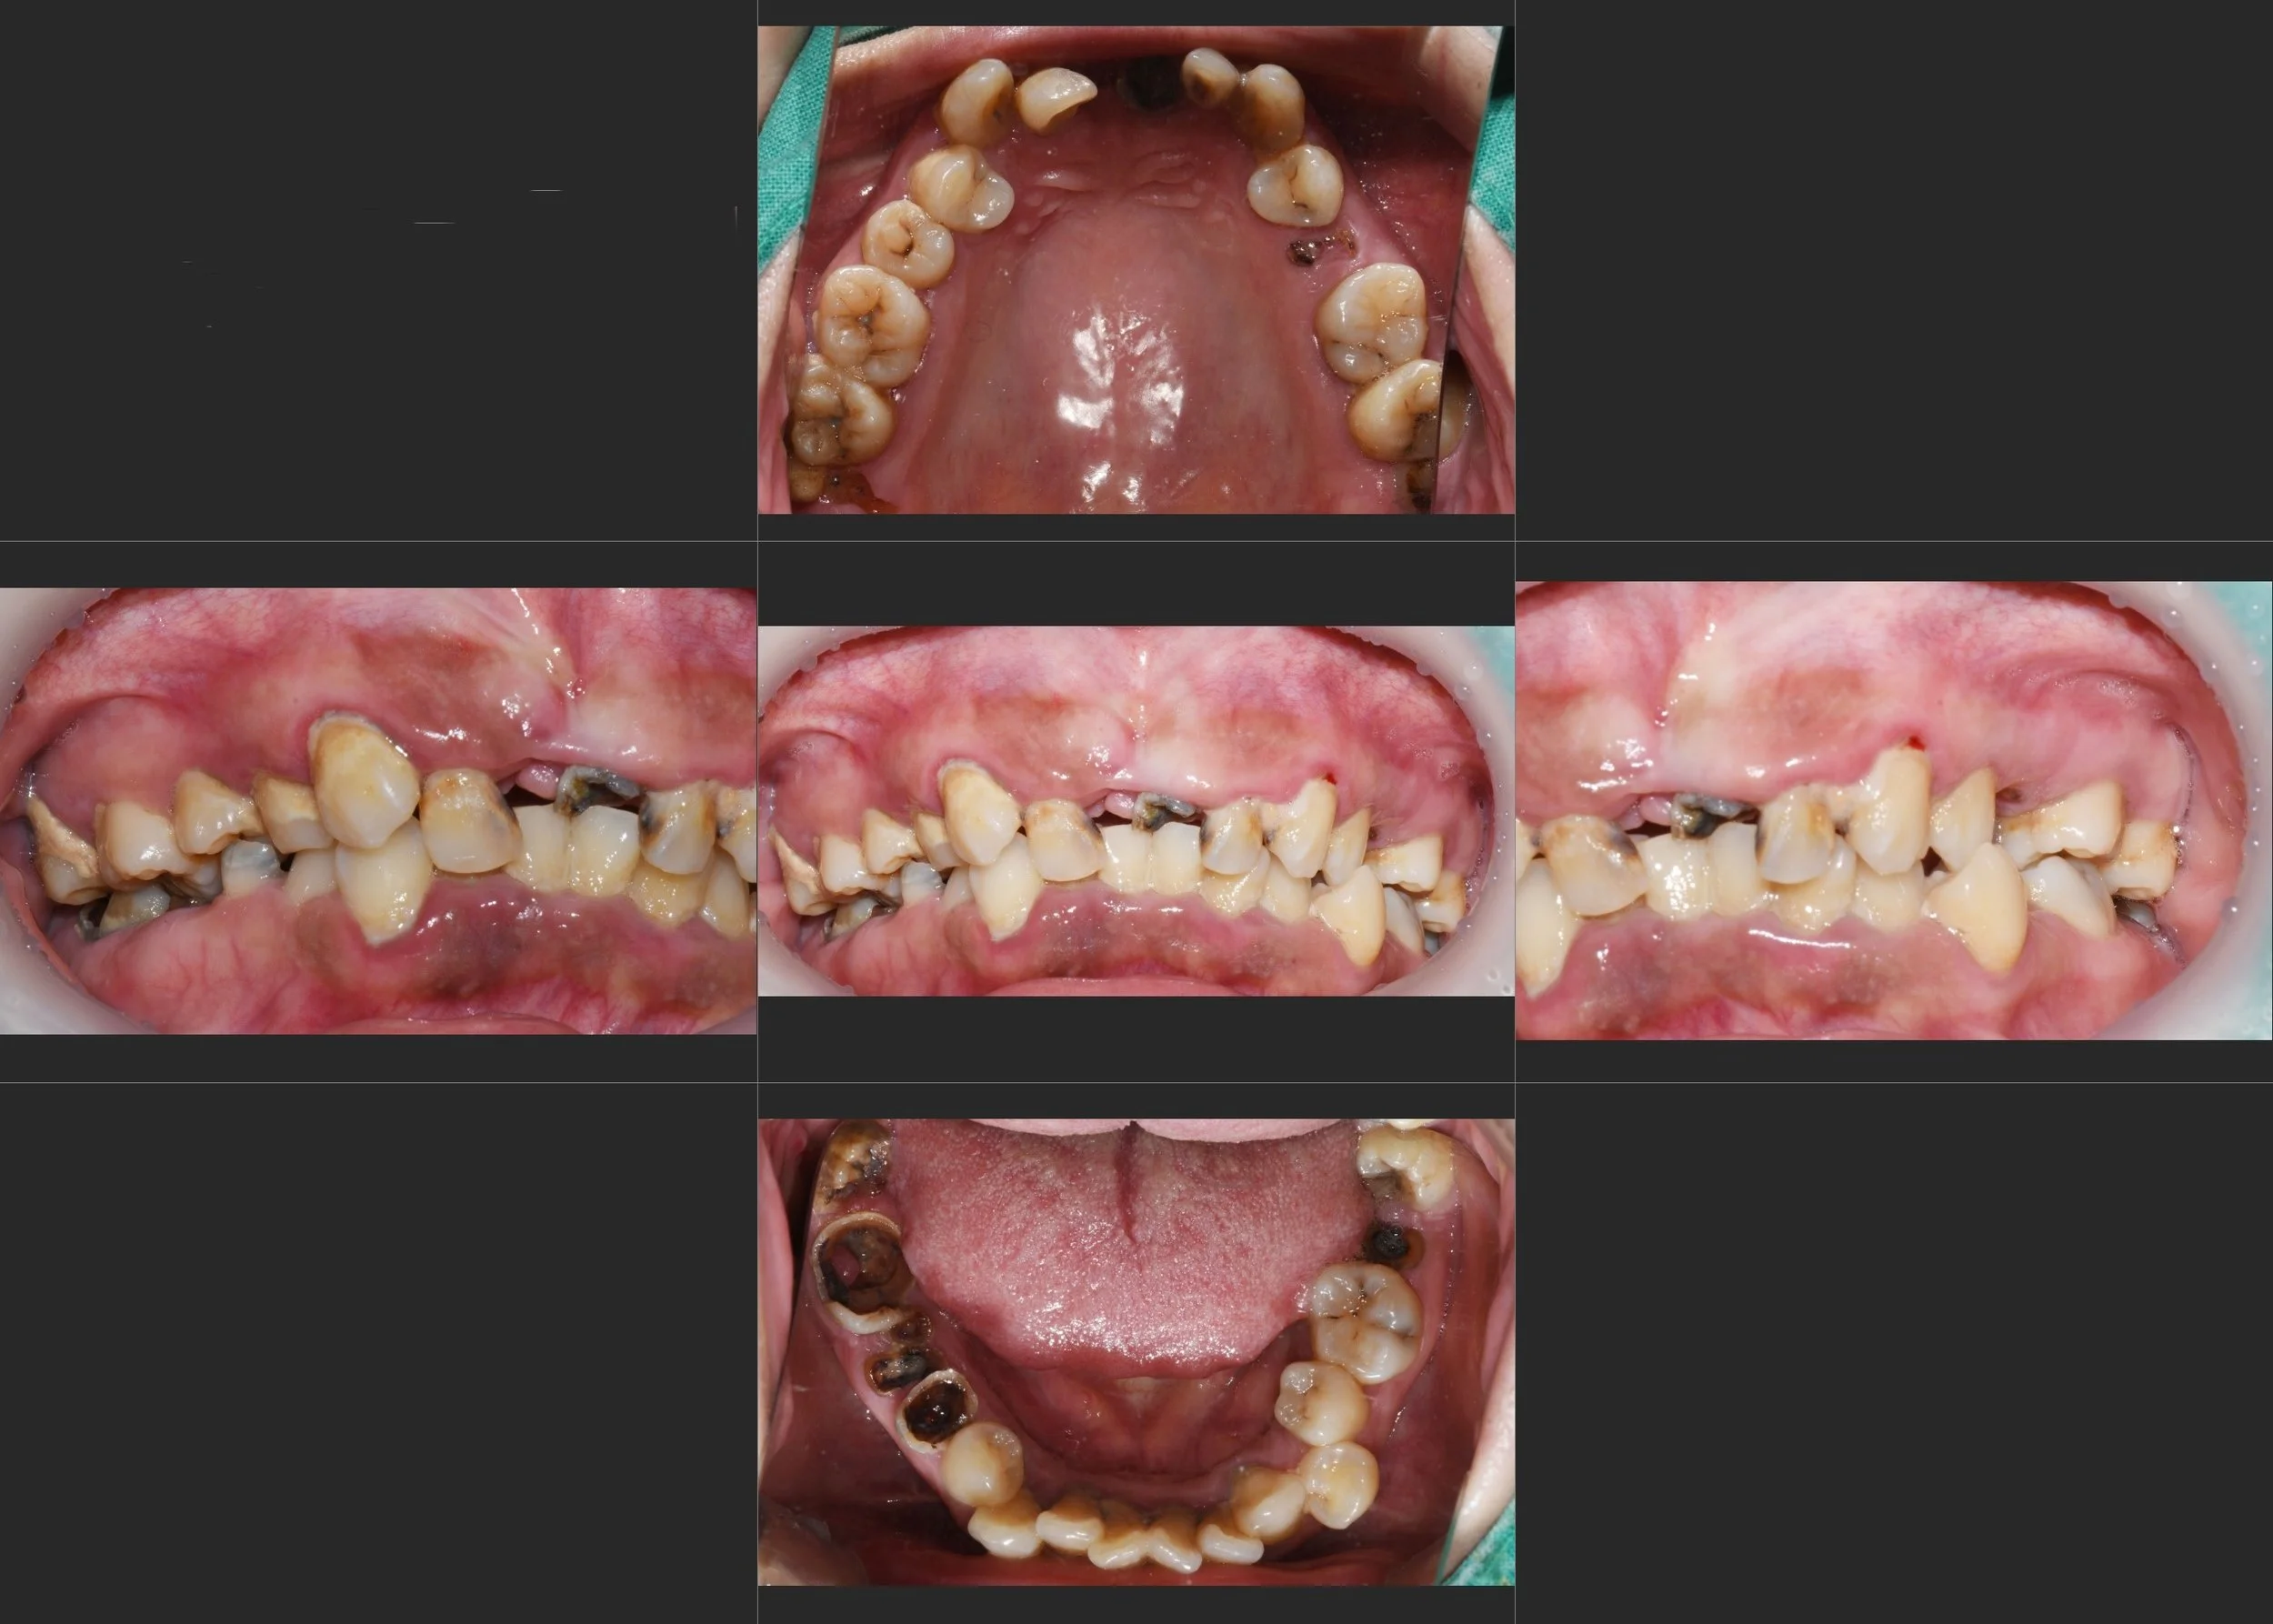

A female patient in her 20s presented with a severely compromised dentition and profound psychological distress. Generalized rampant caries had decimated her remaining teeth, resulting in a completely collapsed occlusion and non-restorable roots throughout both arches.

Due to severe dental phobia, the patient had neglected treatment for years, which had significant psychosocial consequences. She was unable to speak or smile comfortably, constantly wore a face mask, and was suffering from increasing social avoidance.

INTRA ORAL - BEFORE